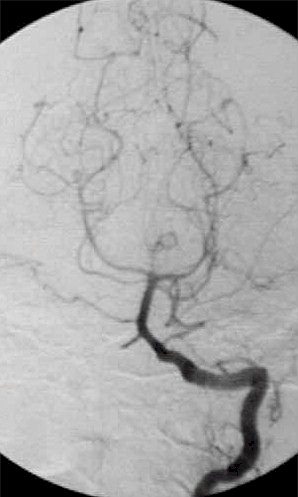

La diagnosi definitiva di aneurisma cerebrale tuttavia è affidata all'angiografia

encefalica che si esegue ponendo un lungo catetere nell'arteria

della coscia, all'inguine, (l'arteria femorale) portandolo fino alle

arterie del collo (carotide e vertebrale) visualizzando tutti i vasi

dell'encefalo. Così si può avere la conferma della presenza

dell'aneurisma e la sua sede.